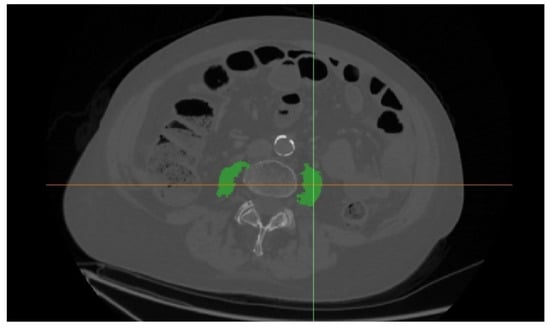

| Median psoas muscle area/height (IQR) (cm2/m) | 7.16 (5.01–9.41) | 7.61 (5.38–9.70) | 5.19 (4.06–7.39) | <0.001 |

| Number of patients with psoas area/height under cut-off point | 94 (36.0%) | 65 (30.2%) | 29 (63.0%) | <0.001 |